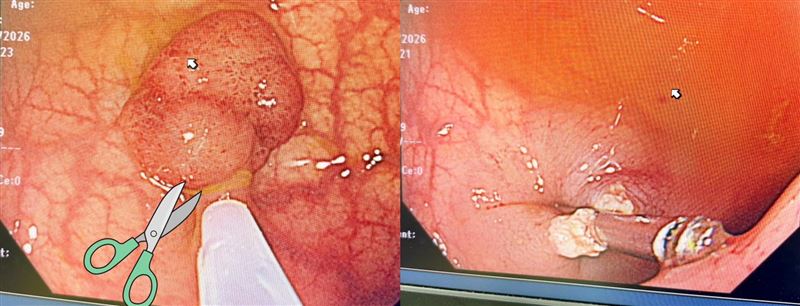

沒有家族病史也可能長出腺瘤性息肉,只有定期大腸鏡檢查,才能及早發現切除,杜絕後患。(圖/翻攝自張靖醫師臉書)

醫師張靖在粉專指出,日前進行大腸鏡檢查時,接連在3名患者腸道內發現巨大息肉。三名患者分別為年輕女性,無大腸癌家族史、健檢糞便潛血陽性(FOBT);中年男性,無大腸癌家族史,也是糞便潛血陽性(FOBT);中年男性,一等親有大腸癌,本身排便習慣改變。

張靖強調,只要出現「糞便潛血陽性」或「一等親大腸癌家族史」情況,一定要進行大腸鏡檢查,才能確認大腸狀況,及時發現腺瘤(Adenoma)才能早點切除,避免未來變成大腸癌。張靖表示,能夠一次幫助3個病人,真的很開心,但也讓他不敢吃香腸、熱狗、培根了。